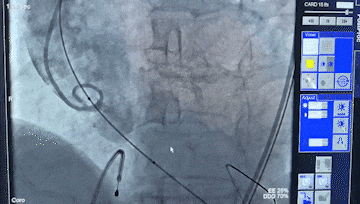

术中造影